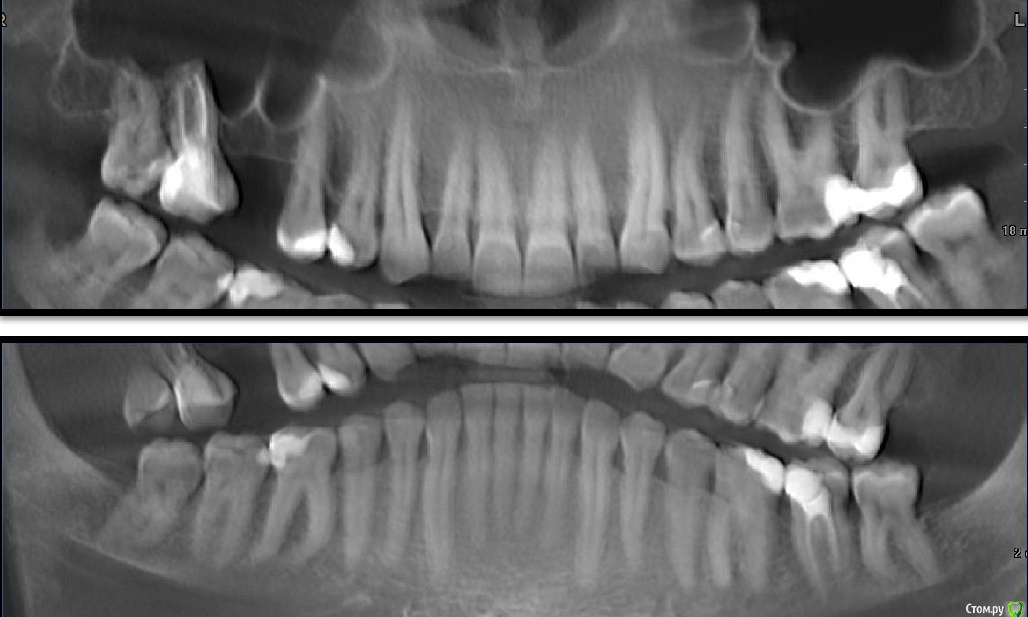

Мне 40 лет, прохожу в данный момент лечение брекетами в связи с открытым прикусом.

Изначально прикус был видимо глубокий, и на протяжении 15 лет беспокоили клиновидные дефекты на верхних резцах, которые постепенно прогрессировали.

Несколько лет назад изза сильного стресса появился бруксизм, резко увеличились клиновидные дефекты, и я некоторое время пользовался ночной капой, изза чего очень быстро появился открытый прикус.

Челюсти стали смыкаться углами зубов мудрости. Долго ходил по врачам, в основном предлагали сделать полное протезирование обеих челюстей, в итоге остановился на ортодонтическом лечении.

Удалили зубы мудрости, прикус стал заметно лучше, поставили брекеты на верх.

Первые 3 месяца все было отлично, пока не заметил, что верхняя семерка слева двигается вверх-вниз где-то на 0,5мм. То есть дуга тянет зуб из кости вниз, а при смыкании челюсти нижний зуб задавливает его обратно.

На следующем приеме врач наклеил на верхние моляры накладки, и выдал резинки для одевания на брекеты на передние верхние и нижние резцы. Первое время было нормально, нагрузка от жевания на двигающийся зуб благодаря накладкам исчезла, однако через некоторое время дуга вытянула этот зуб вниз, контакт при смыкании челюстей опять на нем и он опять двигается. Сейчас ситуация стала даже хуже, чем до удаления зубов мудрости, верхние резцы вообще не перекрывают нижние.

Да, еще мне показалось, что гипсовые модели деформированы сильнее, чем зубы в действительности. Контакт зубов при изготовлении слепков был на последних молярах, а модели почему-то смыкаются в середине челюсти на виде сбоку, а последний моляр висит в воздухе.